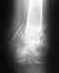

Мне врач поставил диагноз оскольчастый перелом левой пяточной кости.

Посмотрите ,пожалуйста на мои снимки и скажите ваше мнение, пока у меня свежий перелом.спасибо.

Хорошо бы сделать КТ. Будет более отчетливо видно положение сместившегося большого фрагмента суставной поверхности пяточной кости.

Операция здесь вполне уместна, после КТ это будет еще более очевидно. Вот только кто ее будет выполнять, если травматолог, как Вы пишете, всего один, и он настроен негативно.